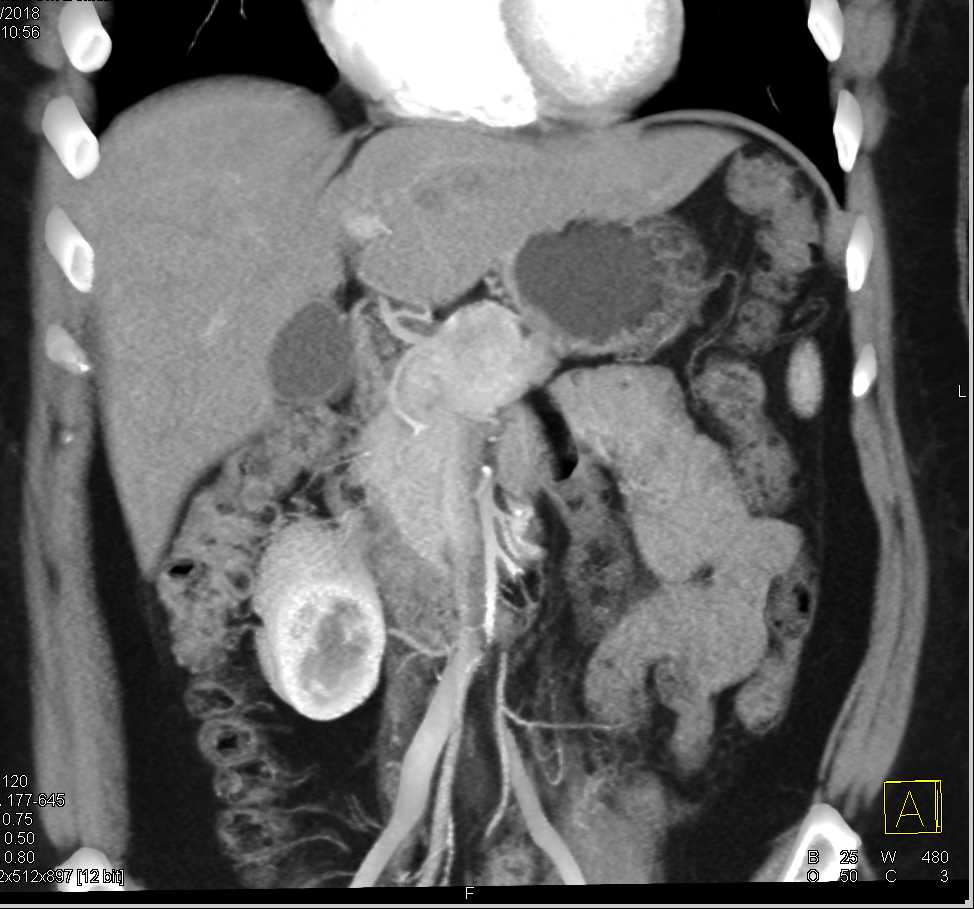

Neuroendocrine Tumor Body of Pancreas